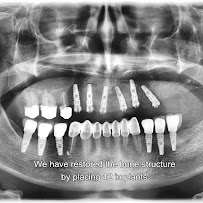

Dental Clinic MEADENT specializes in advanced dental implantology using premium implant systems including Straumann, Zimmer, and BioHorizons brands. The clinic offers innovative All-on-4 and All-on-6 Pro Arch full-mouth implant solutions alongside traditional single and multiple implants. Dental Clinic MEADENT in Belgrade utilizes advanced 3Shape Trios scanners for precise digital smile design and treatment planning before major reconstructive work. The clinic's comprehensive approach encompasses implantology, aesthetic prosthodontics, cosmetic dentistry, orthodontics, periodontology, and oral surgery. Dental Clinic MEADENT in Belgrade combines surgical expertise with aesthetic sensibility, ensuring that all restorations are functional, durable, and naturally beautiful. The team's focus on painless procedures reflects commitment to patient comfort throughout the treatment experience.

Dental Clinic MEADENT specializes in advanced dental implant procedures, offering both traditional implants and innovative full-mouth restoration options. All-on-4 and All-on-6 Pro Arch technologies at Dental Clinic MEADENT in Belgrade allow patients with severe tooth loss to achieve complete dental rehabilitation using minimal implants. The clinic partners with globally recognized implant manufacturers including Straumann, known for long-term clinical success, Zimmer, and BioHorizons. Dental Clinic MEADENT in Belgrade specializes in complex implant cases, including situations requiring bone augmentation using advanced Platelet Rich Fibrin (PRF) technology.